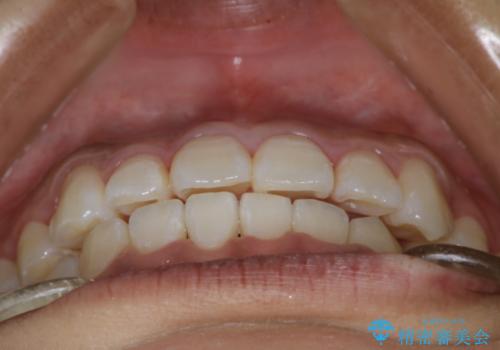

- 前歯の叢生(がたつき)を主訴に来院された患者様です。以前マウスピース矯正をされていたそうでしたが、自身での継続が難しいことなどを理由に、ワイヤー矯正にて改めて矯正治療を希望されました。非抜歯にて治療を計画し治療を行いました。

歯の動きが良く、スムーズに治療を終了しました。一般的にワイヤー矯正はブラッシングが難しいのですが、毎回一生懸命セルフケアをされていたのが印象的です。治療においては、歯の衛生状態も一緒にチェック致します。